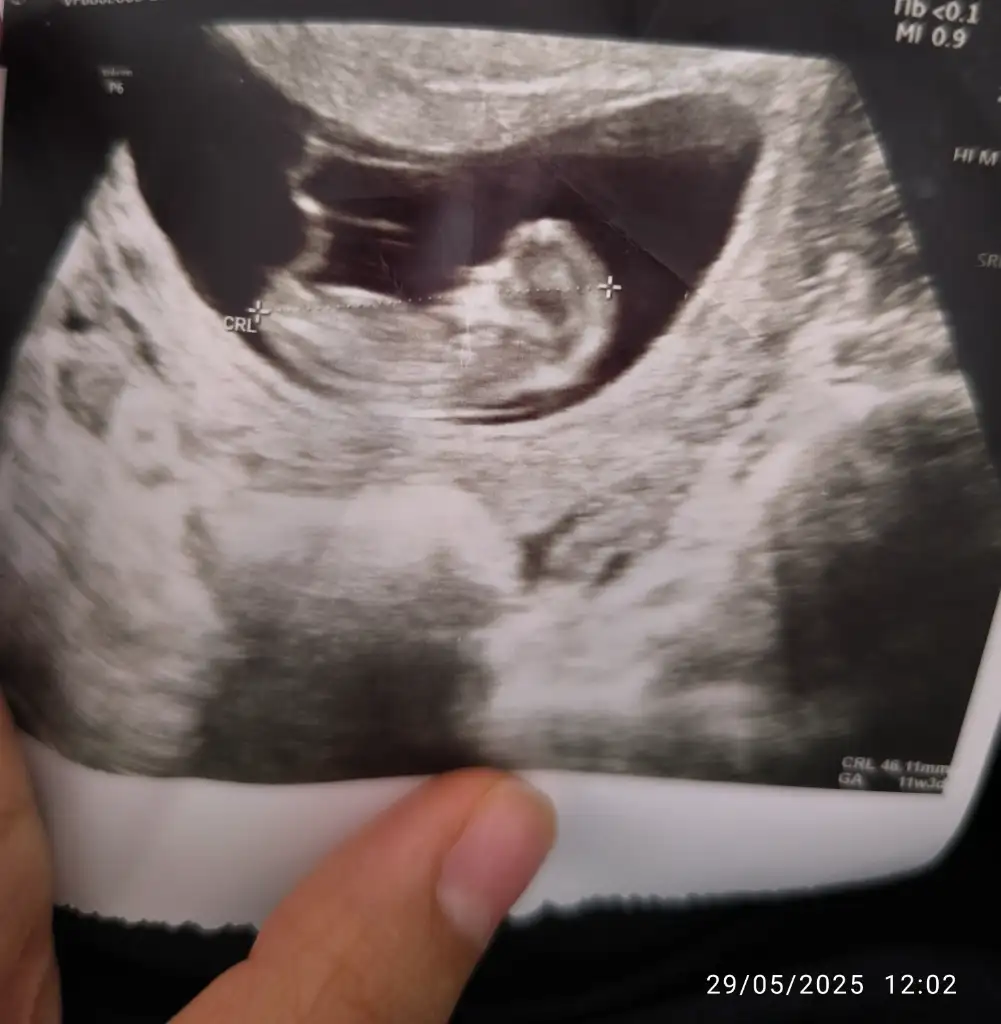

Ultrason görüntüsüne dayanarak gebeliğin yaklaşık 11. haftasında olduğunu görüyorum (aşağıda CRL ve GA bilgisi var). Bu haftalarda bebek henüz cinsiyetini ultrasonla güvenilir şekilde belli edecek kadar gelişmemiştir. Cinsiyet tahmini genellikle 13. haftadan itibaren daha net yapılabilir, ancak en doğru sonuçlar 16. haftadan sonra elde edilir.

1. hafta civarında “nub theory” (tüberkül teorisi) gibi yöntemlerle tahmin yapılmaya çalışılabilir ama bu yöntem bilimsel olarak kesin değildir ve yüksek hata payı içerir.

• Bu görüntüde cinsiyet tahmini yapmak şu an için mümkün değil.

• En doğru tahmin için birkaç hafta sonra tekrar ultrason yaptırmanız önerilir.